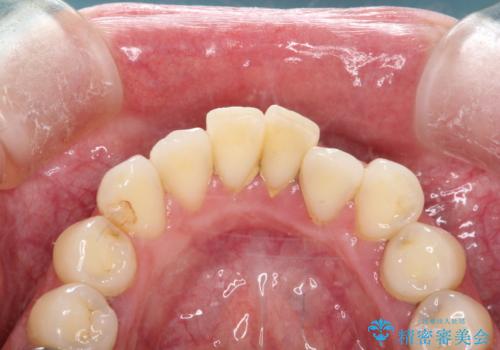

歯周病治療 歯科衛生士による歯石除去

- 数十年ぶりの歯科来院の方です。

歯石は縁下歯石と呼ばれる歯周ポケットを深くして、歯周病を進行させてしまう歯石が沢山有りました。

虫歯治療や歯石除去を済ませてから、矯正治療(インビザライン)を開始する患者様です。